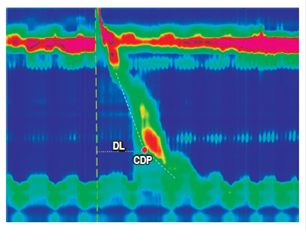

DL is the time interval in seconds between the relaxation of the UES and the inflection point along the isobaric contour of 30 mm Hg where the velocity of propagation slows. This point is known as the contractile deceleration point (CDP), and it demarcates the tubular esophagus from the phrenic ampulla. DL is an indirect measure of swallowing inhibition and, therefore, of normal peristalsis. A measurement of less than 4.5 seconds defines a premature contraction (Figures 6 and 7)9.

Figure 6 DL is the time interval in seconds between relaxation of the UES and the CDP (red dot). The CDP is the point along the isobaric contour of 30 mm Hg at which the speed of propagation slows down. It demarcates the tubular esophagus from the phrenic ampulla.